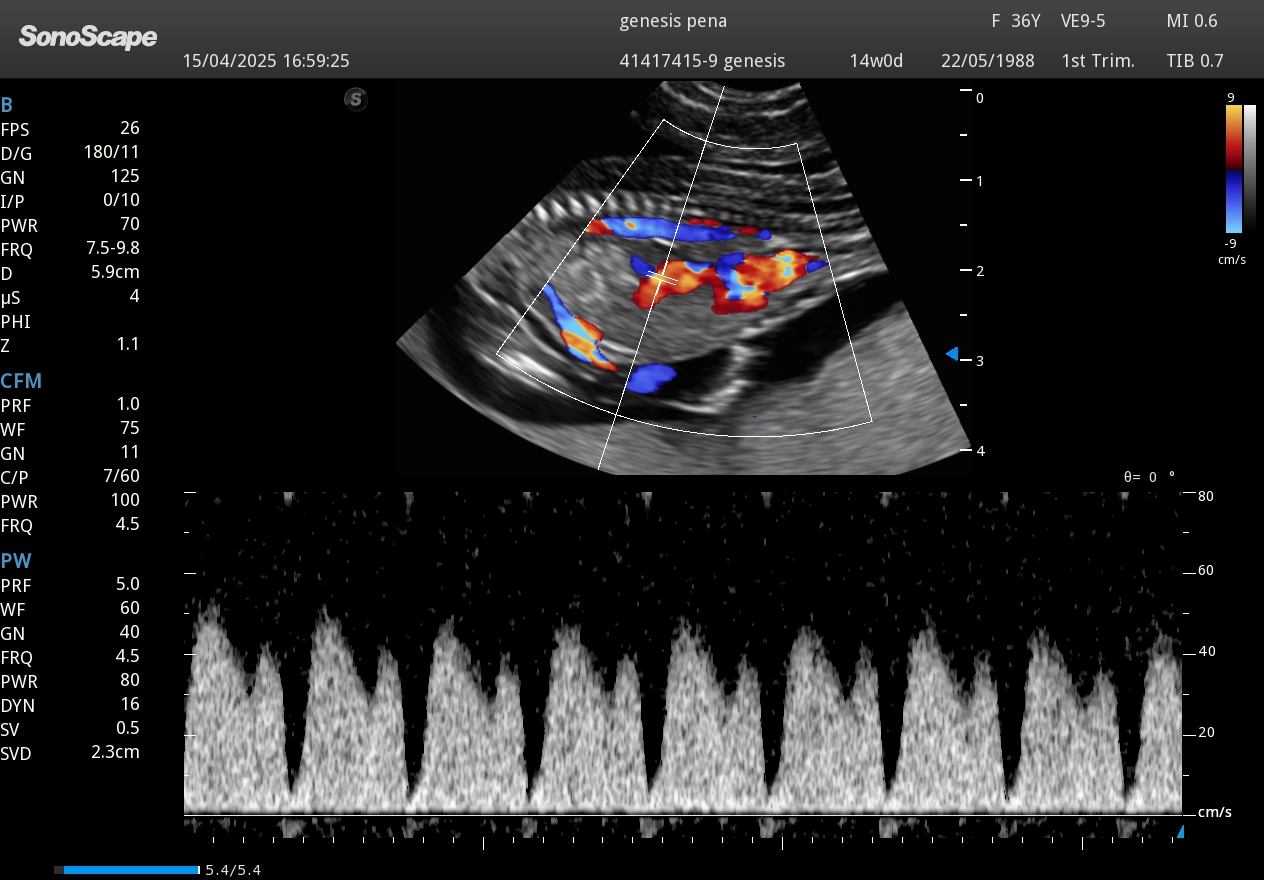

Doppler flujo umbilical fetal embarazo

Doppler pulsado para evaluación del flujo sanguíneo umbilical fetal.